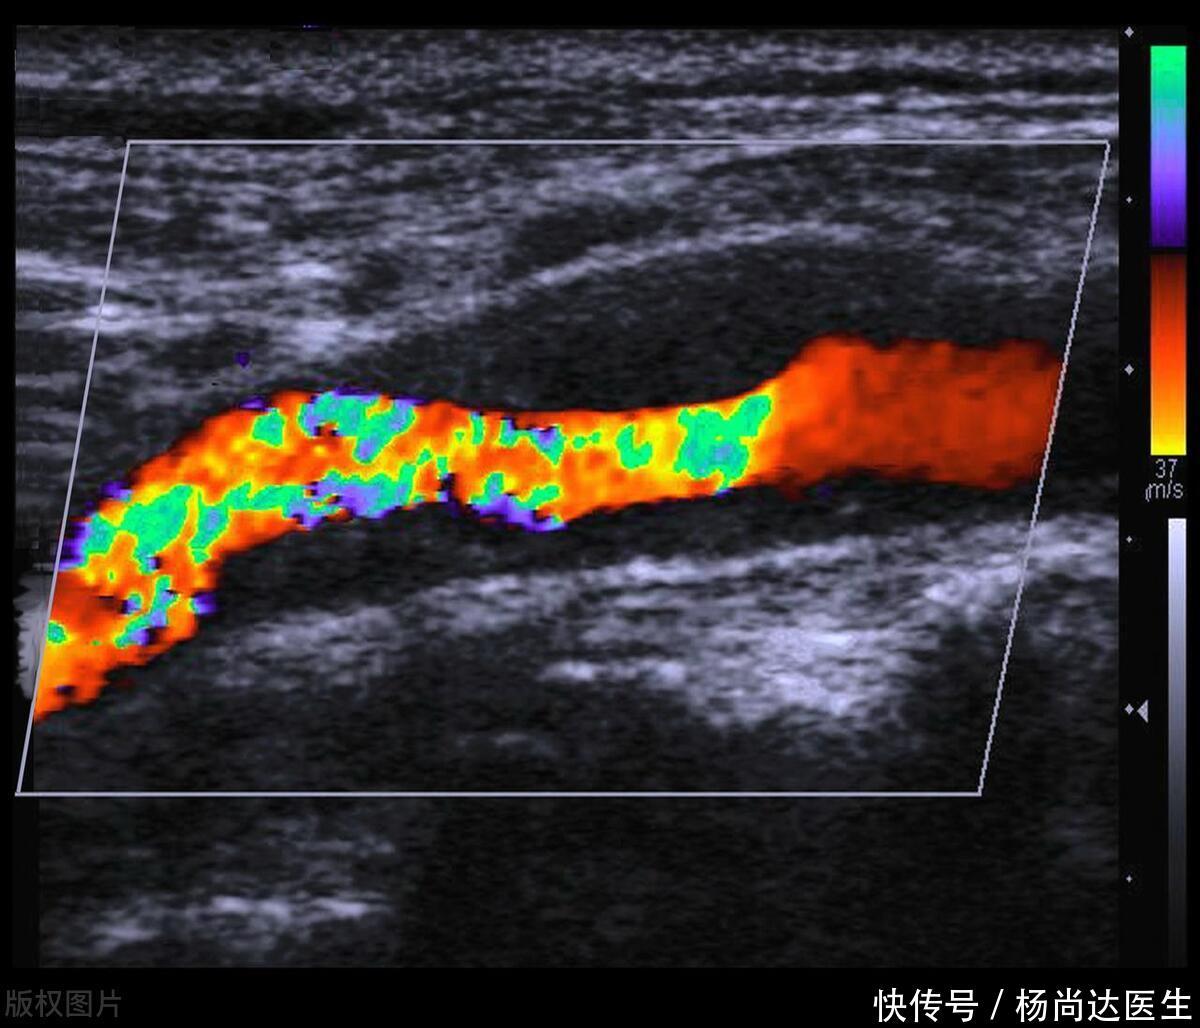

其次,需要注意斑块的回声特性,这对于进一步评估动脉状况至关重要。在超声报告中,斑块通常以低回声、等回声、高回声或混合回声等形式描述。其中,低回声斑块往往意味着其内部成分较为松散,更易于脱落形成血栓,因此风险较高。这就像河道中的松散泥沙,一旦水流湍急,很容易被冲走形成泥石流。

再次,需要关注斑块的稳定性,这是评估动脉疾病严重程度和治疗方案的重要指标。稳定的斑块表面光滑,与血管壁贴合紧密,不易脱落;而不稳定的斑块则表面粗糙,容易破裂,形成血栓的风险也就更高。这就像河堤的稳固性,稳固的河堤能够抵御洪水的冲击,而松散的河堤则容易在洪水来临时崩塌。

最后,要定期进行超声检查。通过超声检查,我们可以及时了解斑块的变化情况,以便采取相应的治疗措施。这就像定期检查河道的淤积情况一样,只有了解了实际情况,才能做出正确的应对。